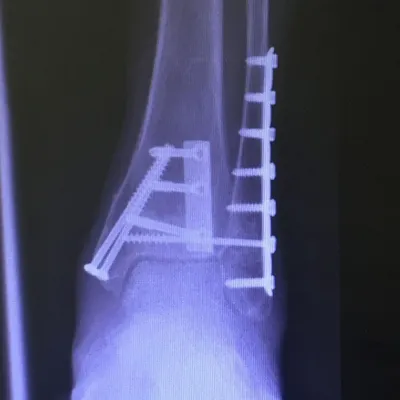

Preop and Postop Trimalleolar Fracture with Fixation of Posterior Malleolus Fracture

Preop

Postop